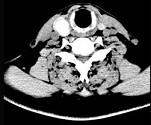

问题 男,43岁,因右颈部扪及一包块来院就诊。如图所示该患者应诊断为 ( )

选项 A、甲状腺原发淋巴瘤 B、甲状腺转移瘤 C、甲状腺腺癌 D、结节性甲状腺肿 E、甲状腺腺瘤

答案 E